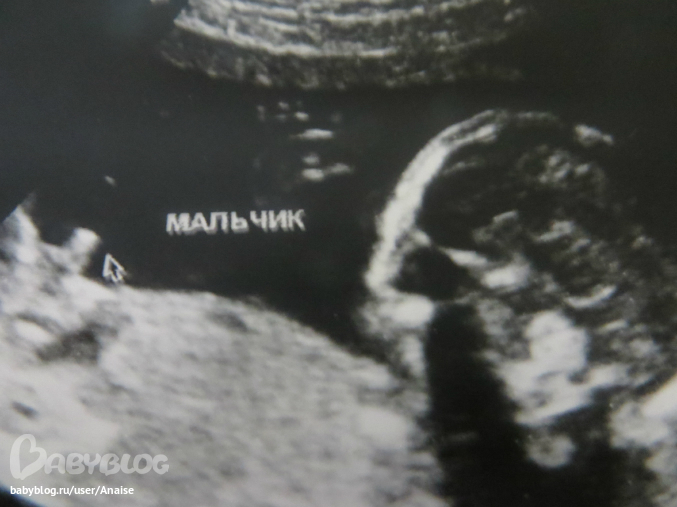

Анализы, скринингиМальчик остался мальчиком.

Свистулька наша на месте. Малыш у нас растет совсем не скромный. Все свои причендалы вывалил нам моментально. Зато личико старательно прятал ручками. Игрался с пуповиной, зевал, сосал пальчик. В общем развлекался пока мы на него глазели.

Сын (блин это так гордо вычит!) как и в прошлый раз обгоняет срок ровно на 1 день. т.е. по узи у нас 19 недель и 1 день. ПДР по месячным 8.08.13, по узи 7.08.13.